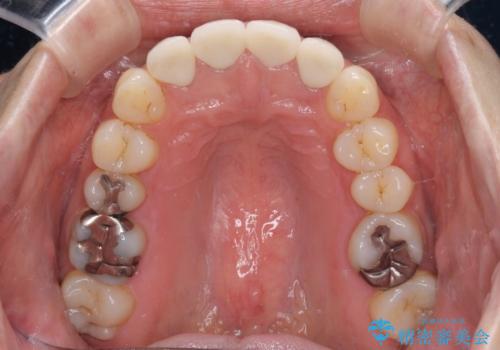

- 前歯のクラウンの変色や歯の変色を気にして来院された患者様です。

グラスファイバーを用いた土台により歯質を強化した上で、オールセラミッククラウンにて補綴することとしました。

統一感があり、歯肉ラインもきれいに整い、清潔感溢れる口元に仕上げることができました。